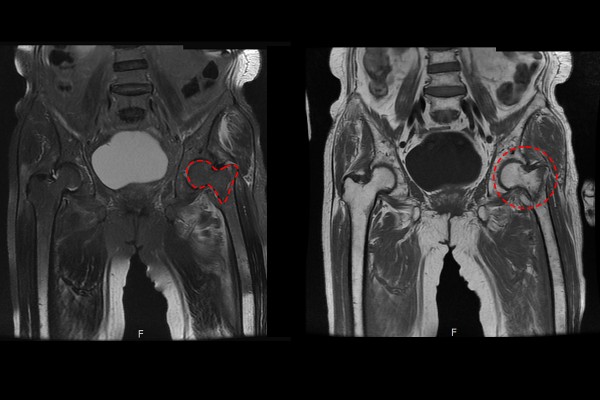

자세한 검사를 위하여 MRI 촬영을 진행하였고, 촬영한 MRI에서도 대퇴경부목 골절이 확인되어 고관절 골절 (대퇴골 경부 골절)(Fx. femur neck hip Lt. (Garden type IV))을 진단하였고, 보호자분께 수술적 치료의 필요성을 설명드렸습니다.